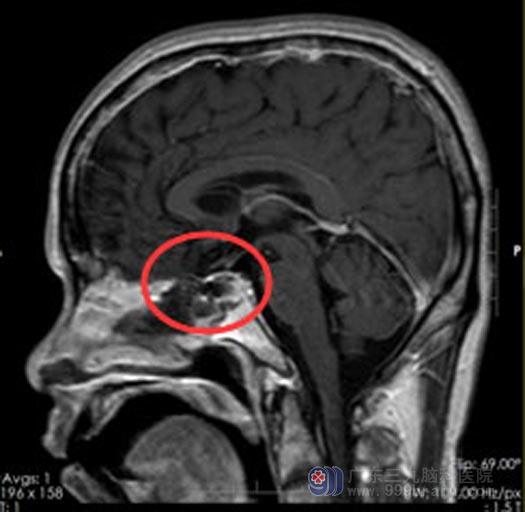

经家属同意后,在全麻下行内镜经鼻蝶鞍区占位切除术,手术很顺利。术后病理:鞍区促性腺激素垂体腺瘤。

手术后